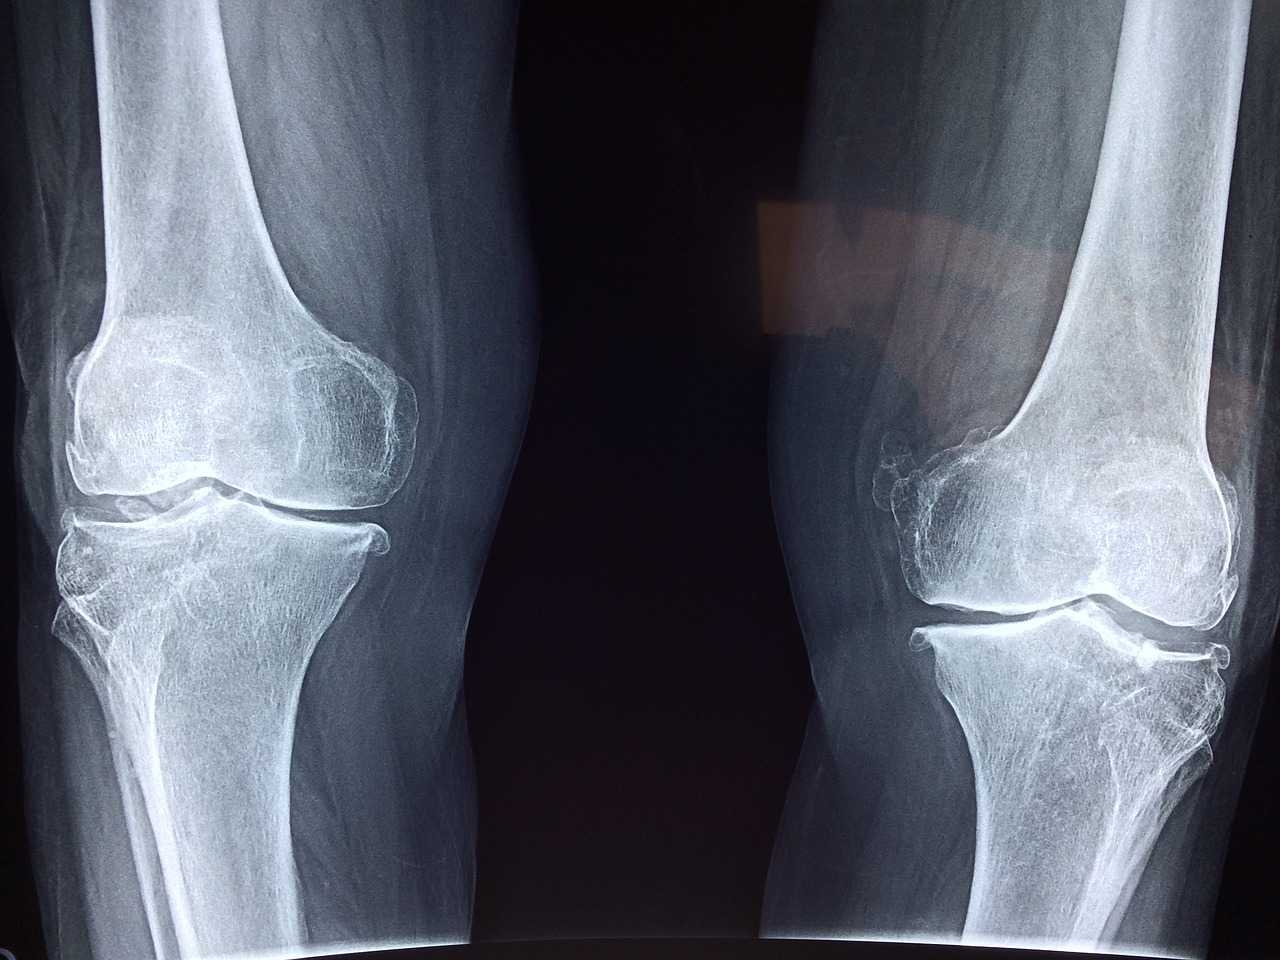

Gadge Hospital is orthopedic hospital for specialized care in bone and joint health near you . We offer individualized care with state-of-the-art equipment and caring professionals to guarantee your recovery and wellbeing. For more visit us!